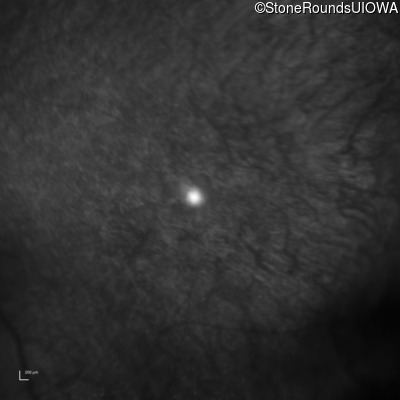

Infrared Fundus Photograph - Right - 10/200

Exemplar